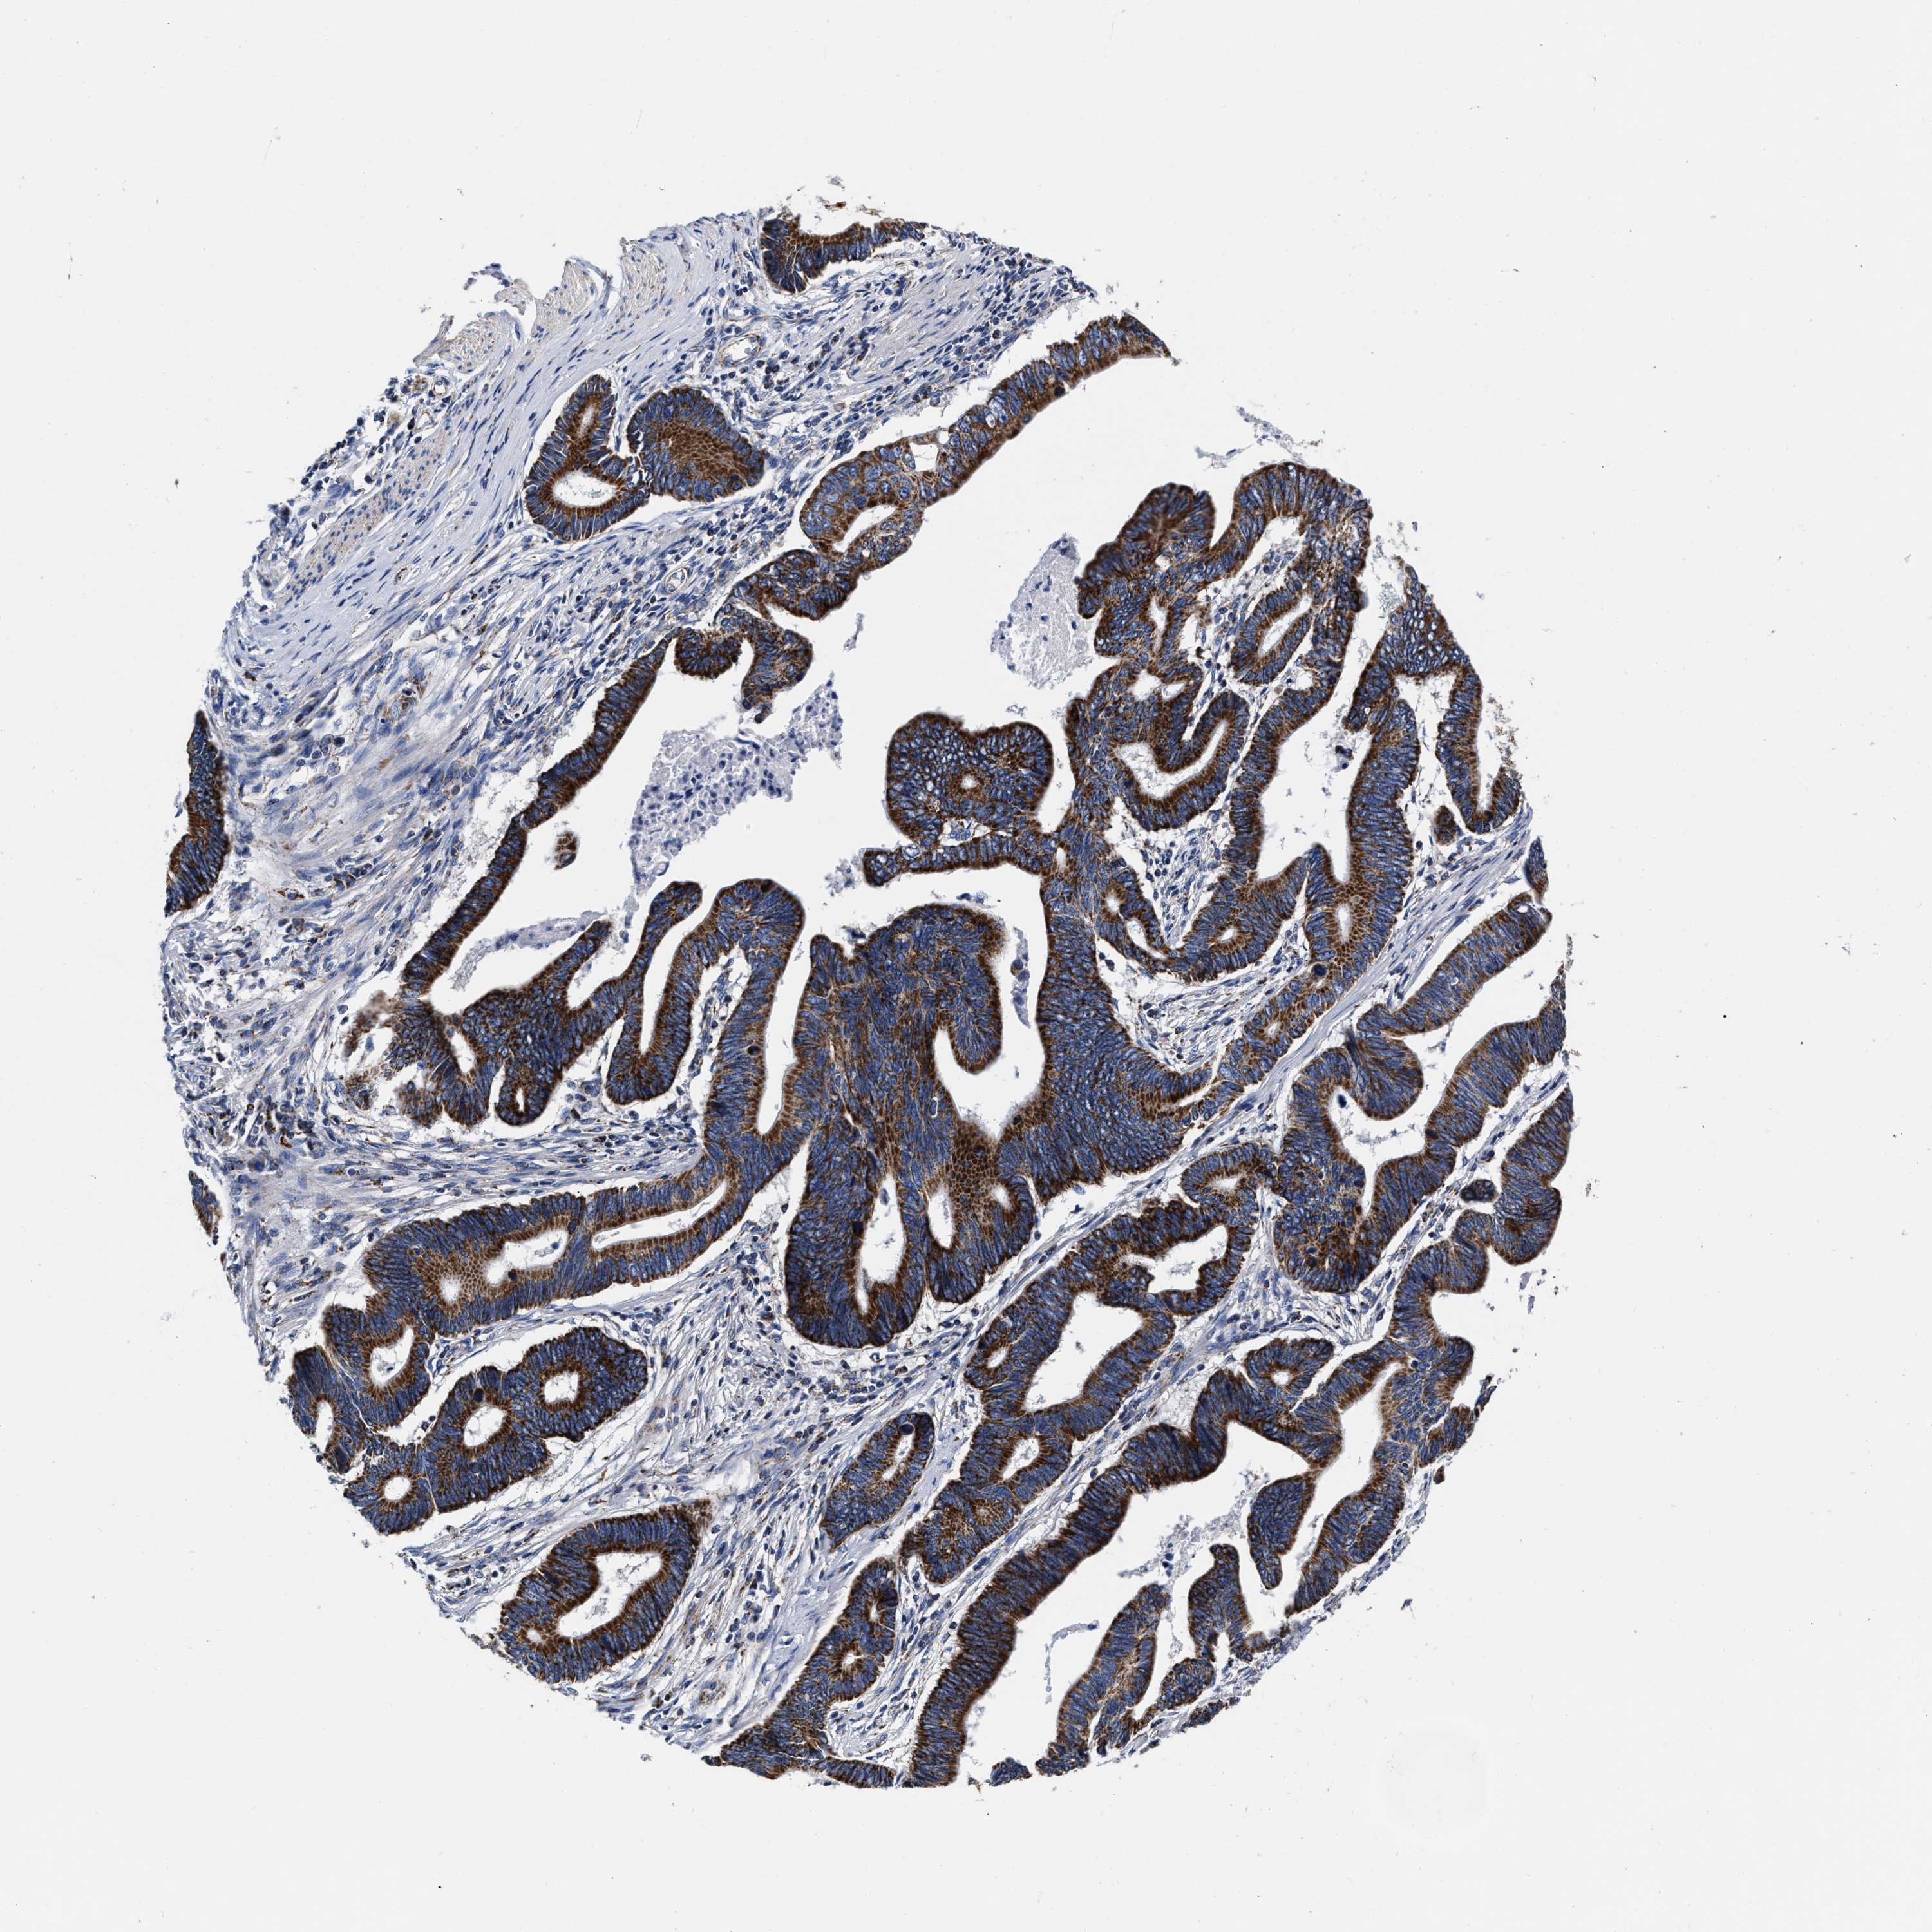

PANCREATIC CANCER - Protein expressioni

A mouse-over function shows sample information and annotation data. Click on an image to view it in a full screen mode. Samples can be filtered based on level of antibody staining by selecting one or several of the following categories: high, medium, low and not detected. The assay and annotation is described here.

Note that samples used for immunohistochemistry by the Human Protein Atlas do not correspond to samples in the TCGA dataset.

Antibody stainingi

Antibody staining in the annotated cell types in the current human tissue is reported as not detected, low, medium, or high, based on conventional immunohistochemistry profiling in selected tissues. This score is based on the combination of the staining intensity and fraction of stained cells.

Each image is clickable and will lead to virtual microscopy that enables deeper exploration of all samples and also displays staining intensity scores, fraction scores and subcellular localization as well as patient and tissue information for each sample.

Antibody HPA020961

Antibody HPA059109

Adenocarcinoma, NOS